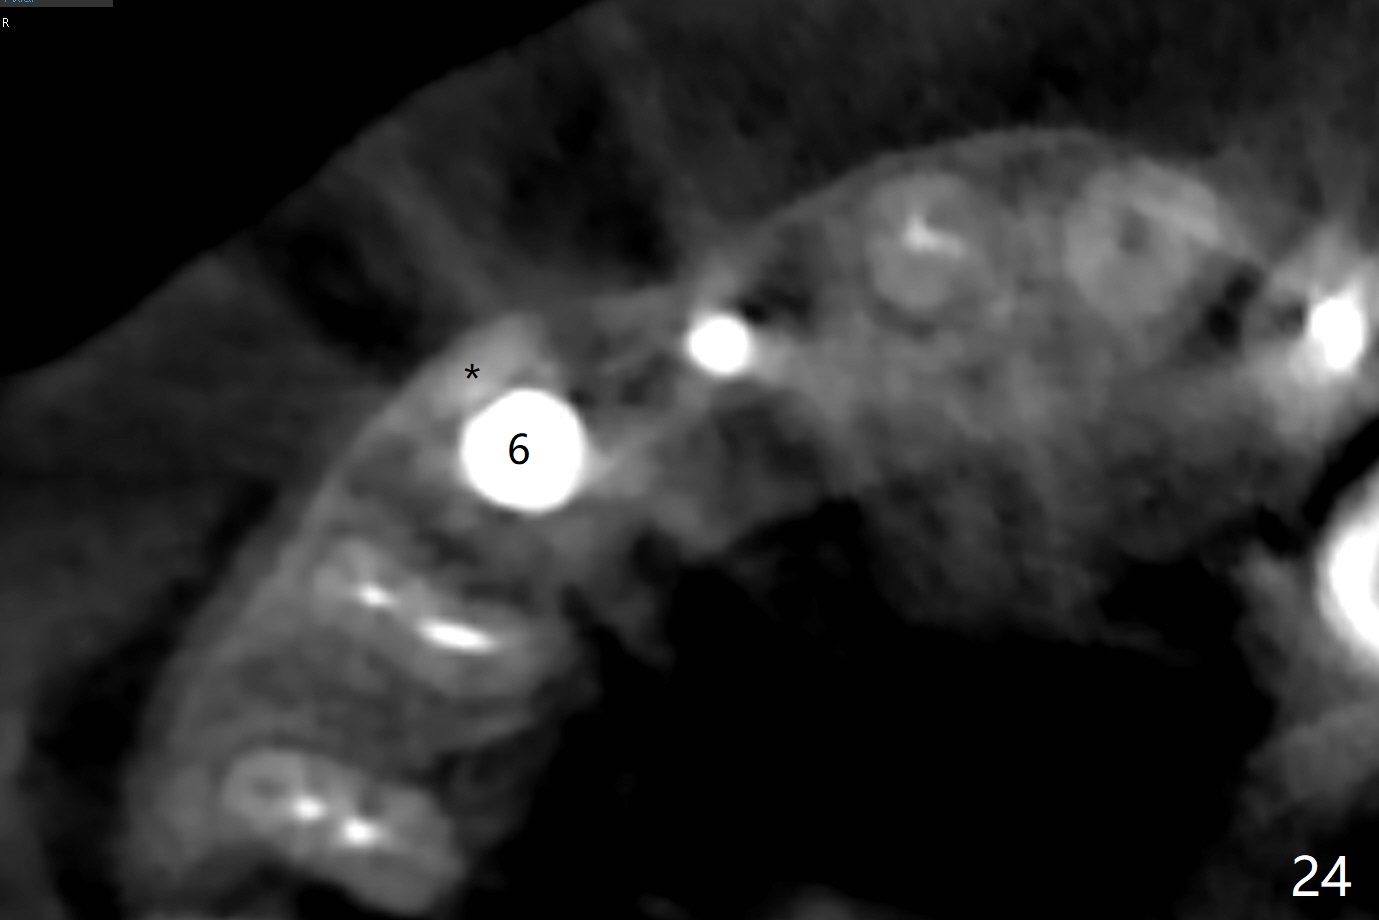

When the bridge is sectioned between #7 and 8, the tooth #6 is found non-salvageable (Fig.1).  Incision shows the atrophic buccal plate at #7 (Fig.2 arrowheads); to prevent the same feature from happening at #6 with thin buccal plate, the most buccal portion of the root is preserved (socket shield (Fig.2-4: *)).  The initial osteotomy is established in the palatal slope at #6 (Fig.5 circle) with 1.5 mm drill (Fig.6,7).  A portion of the root is visible in Fig.6 (arrowheads).  After sequential osteotomy with 2 mm, 3 mm (Fig.8) and 3.2 mm drills, a 4x15 mm implant is placed (Fig.10).  To accommodate the cross bite, the coronal portion of the implant (Fig.9 white circle) is positioned close to the socket shield.  It appears that the shield prevents the implant from encroaching the buccal plate.

Since the ridge at #7 is ~ 4 mm, a 2.5x14 mm 1-piece implant is placed (Fig.8) after 1.2 mm (Fig.7), and 1.5 mm drills at 12 mm and 2 mm drill at 8 mm.  Later the implant is placed deeper (Fig.10).  There is no bone loss 7 or 12 months postop, respectively (Fig.11,12).  After Diode gingivectomy, there is papillary formation (Fig.13).  No provisional is provided after impression (with the abutment torqued at #6) for oral hygiene.  With access holes at #6 and 7, crowns are bonded with minimal residual cement (Fig.14 <, which is removed later).  There is no hard (Fig.15,16) or soft (Fig.17 *) atrophy 26 months postop, i.e., 13 months post cementation, due to the presence of socket shield (Fig.15 <, as compared to Fig.1).  In fact the tooth #8 has mobility and fremitus (short root/poor crown/root ratio, Fig.16); occlusal adjustment is done 13 months post cementation.  The crown is dislodged 2 years 1 month post cementation; a prefabricated post is being tried in (Fig.18).  There is no atrophy, bone loss or infection at #6 (with socket sheath (*)) or 7 two years 5 months post cementation (Fig.20-27).